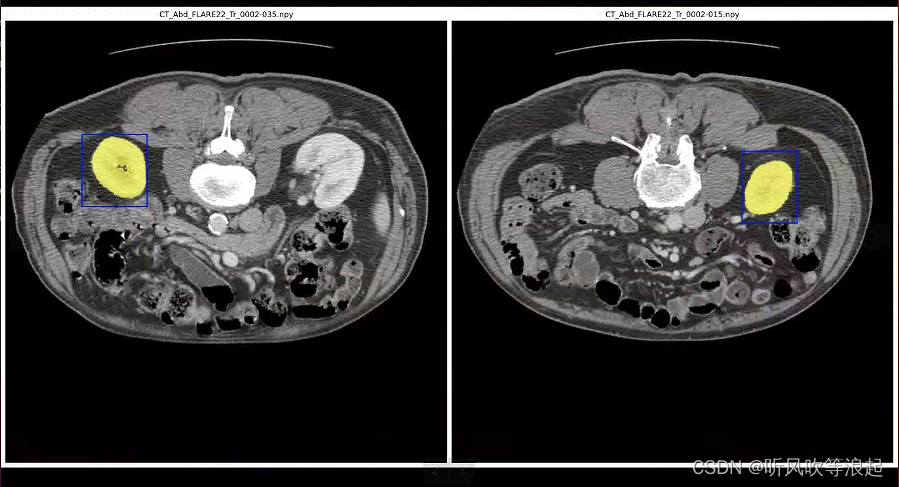

可视化结果: